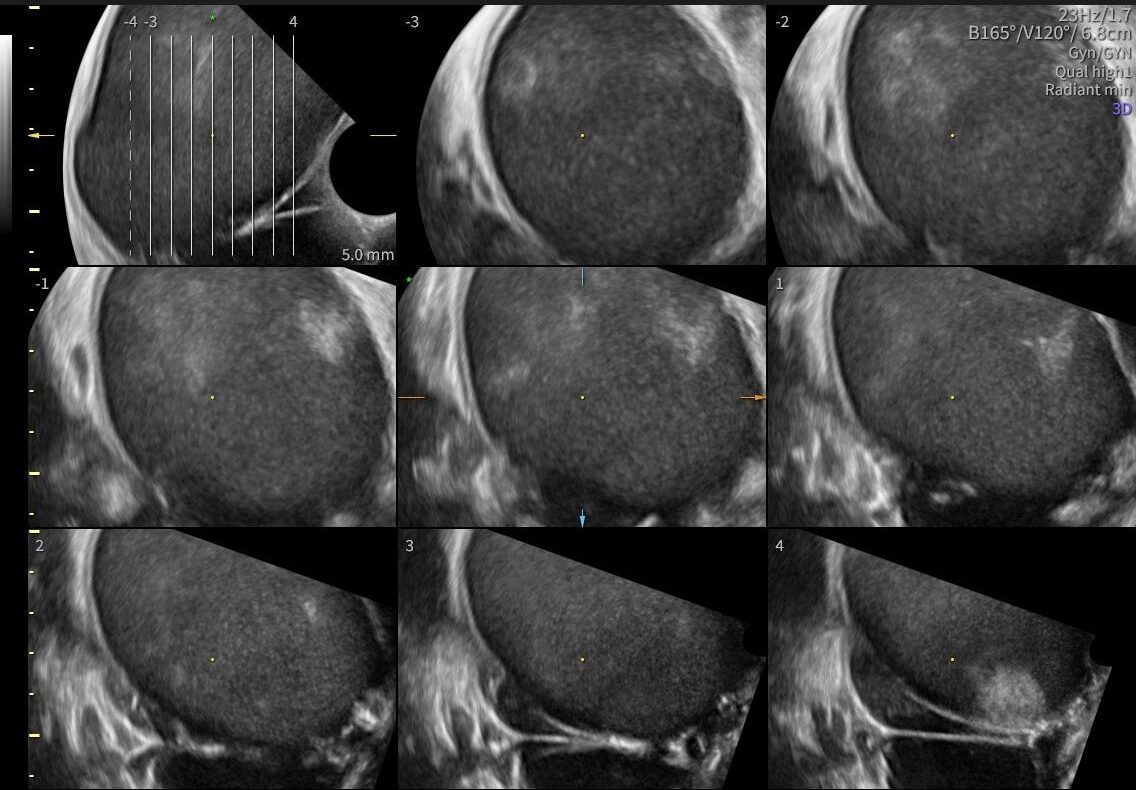

La ecografía ginecológica es un estudio por imágenes no invasivo que permite evaluar de forma precisa el útero, los ovarios y el sistema reproductor femenino. Es una herramienta fundamental para la detección temprana de alteraciones ginecológicas, el seguimiento de tratamientos y los controles preventivos.

En OBGYN Perú, realizamos ecografías ginecológicas con equipos de alta resolución, garantizando resultados confiables y una atención médica especializada.